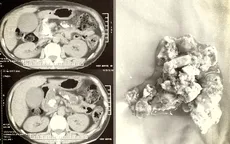

Phẫu thuật lấy sỏi ống tụy kích thước lớn hiếm gặp cho bệnh nhân VTV.vn - Bệnh viện Hoàn Mỹ Đà Nẵng vừa phẫu thuật thành công, lấy sạch sỏi san hô ống tụy kích thước lớn, hiếm gặp cho nữ bệnh nhân 50 tuổi.